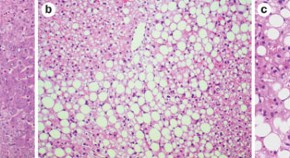

Nonalcoholic fatty liver disease (NAFLD) and/or nonalcoholic steatohepatits can take decades to evolve and progress, which limits the quality of longitudinal data. Researchers have, therefore, turned their attention to the development of suitable animal models to test the role of molecules and molecular pathways in the progression of fatty liver formation. This Review discusses the benchmark animal models that recapitulate the pathology and metabolic dysfunction associated with NALFD.